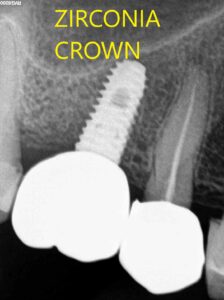

Successful case gallary